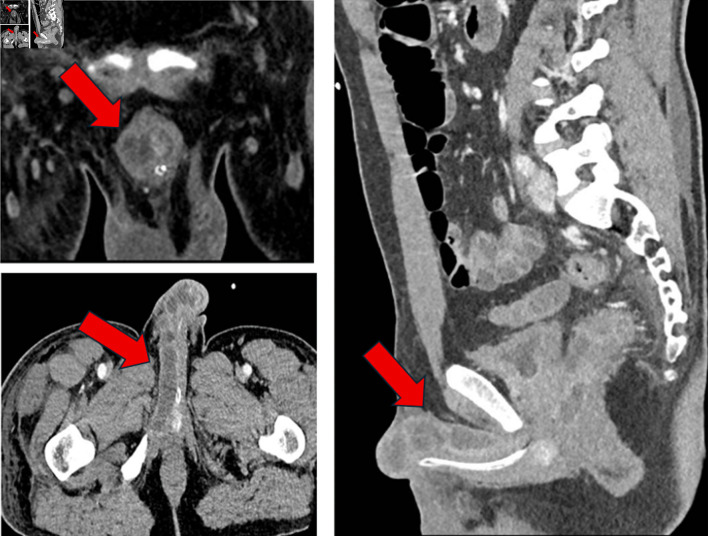

结直肠癌(CRC)向海绵体转移是一种非常罕见的疾病,通常与全身传播和预后不良有关。它常与肝脏和淋巴结累及同时出现。男性,43岁,会阴疼痛,直肠出血,尿路梗阻症状。影像学检查显示kras突变的直肠腺癌,分类为IV期,同步转移到海绵体和肝脏。治疗开始时采用FOLFOXIRI(亚叶酸、5-氟尿嘧啶、奥沙利铂和伊立替康)化疗,但由于肿瘤溶解综合征和与UGT1A1突变相关的毒性而停止。尽管改良FOLFOX(亚叶酸、氟尿嘧啶、奥沙利铂)加贝伐单抗,但病情进展迅速,促使患者转向姑息治疗,随后死亡。海绵体累及CRC反映疾病进展,经常伴有同步转移和有限的预期寿命。该病例强调了此类转移的不良预后意义,提示盆腔淋巴扩散可能是一种机制,并强调了药物遗传学对治疗耐受性和结果的关键影响。文献回顾强调了这种表现的侵略性生物学。结直肠癌的阴茎转移是罕见的,但具有破坏性,表明疾病是播散性的。多学科管理应优先考虑症状控制,并保留针对特定病例的靶向治疗。本病例说明有泌尿系统症状的恶性肿瘤病史的患者需要加强临床怀疑。

Metastasis to the cavernous bodies from colorectal cancer (CRC) is an exceptionally rare condition, typically associated with systemic dissemination and an ominous prognosis. It often presents synchronously with liver and lymph node involvement. A 43-year-old male presented with perineal pain, rectal bleeding, and urinary obstructive symptoms. Imaging studies revealed a KRAS-mutated rectal adenocarcinoma, classified as stage IV, with synchronous metastases to the cavernous bodies and liver. Treatment was initiated with FOLFOXIRI (folinic acid, 5-fluorouracil, oxaliplatin and irinotecan) chemotherapy but was discontinued due to tumor lysis syndrome and toxicity linked to a UGT1A1 mutation. Despite modified FOLFOX (folinic acid, fluorouracil, oxaliplatin) plus bevacizumab, the disease progressed rapidly, prompting transition to palliative care and subsequent death. Cavernous body involvement in CRC reflects advanced disease, frequently accompanied by synchronous metastases and a limited life expectancy. This case underscores the poor prognostic significance of such metastases, suggests pelvic lymphatic spread as a likely mechanism, and highlights the critical impact of pharmacogenetics on treatment tolerance and outcomes. A review of the literature emphasizes the aggressive biology of such presentations. Penile metastases from CRC are rare but devastating, indicating disseminated disease. Multidisciplinary management should prioritize symptom control, with targeted therapies reserved for select cases. This case illustrates the need for heightened clinical suspicion in patients with a history of malignancy presenting with urological symptoms.